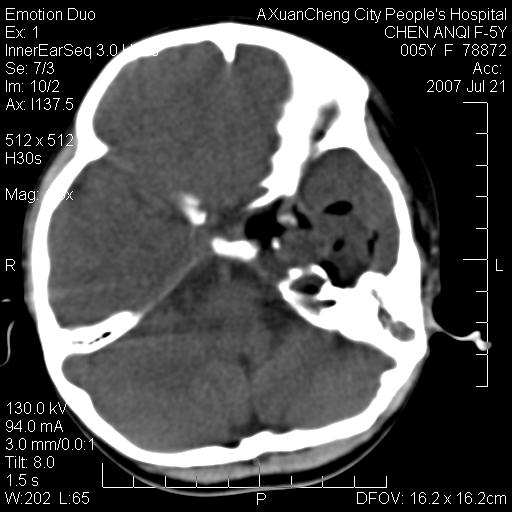

标题: PED0273:5岁,左耳流脓痛疼一周,颅底骨质破坏 [打印本页]

标题: PED0273:5岁,左耳流脓痛疼一周,颅底骨质破坏

患儿5岁,左耳流脓痛疼一周,左外耳道肉芽组织填塞 软组织窗显示病灶内结节状低密度影为气体密度

1.左耳中耳炎. 2.考虑伴颅内感染.

颅底骨质破坏,建议增强扫描

感觉不象恶性的

补充:腺样体肥大.